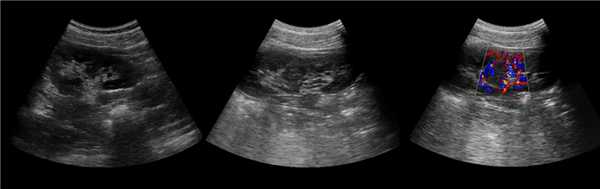

Клинический пример из второй группы. Пациент К. перенес операцию пересадки почки от живого родственного донора. Трансплантат в левой подвздошной области. Индекс резистентности в междольковых артериях составил 0,70 (рис. 5). В сегментарных артериях индекс резистентности составил 0,66 (рис. 6). Показатели жесткости паренхимы почечного трансплантата при режиме УЭСВ составили от 31,6 до 36,9 кПа (рис. 7-9).

Рисунок 5. Исследование у пациента К. в режиме цветовой и спектральной допплерографии. Индекс резистентности в междольковых артериях почечного трансплантата составил 0,70

Рисунок 6. Эхограмма пациента К. Кровоток в сегментарных артериях неизменен